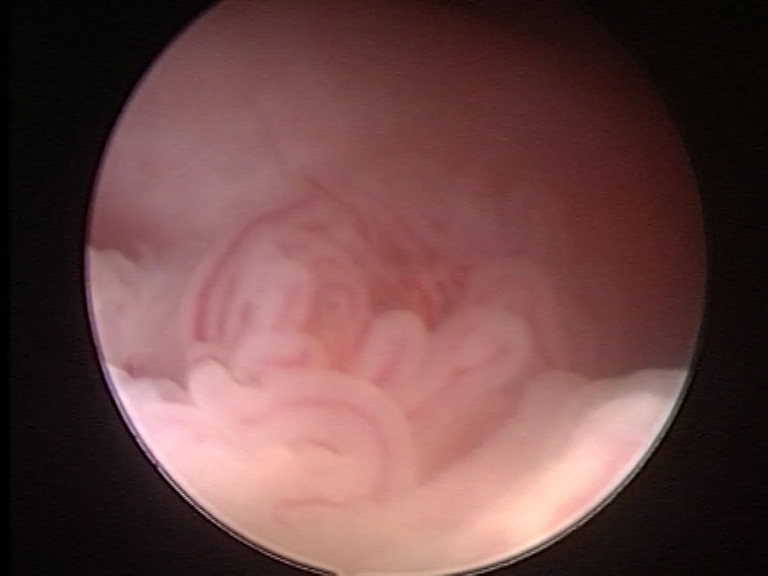

L’isteroscopia è una tecnica mini-invasiva endoscopica che, attraverso l’uso di un’ottica con telecamera sottilissima e di strumenti adeguati, consente di diagnosticare (isteroscopia diagnostica) e curare (isteroscopia operativa) diverse condizioni patologiche.

L’isteroscopia diagnostica diviene utile nel caso di sanguinamenti uterini anomali, tanto nell’età fertile quanto e soprattutto dopo la menopausa, ed è possibile evidenziare malformazioni uterine come setti, patologie della cavità dell’utero come polipi, fibromi, iperplasie o in alcuni casi tumori maligni.

Galleria immagini